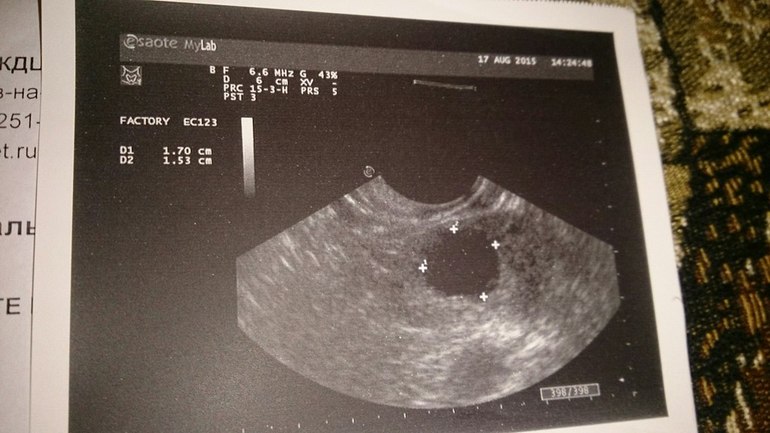

Подскажите, пожалуйста, на какой ДЦ мне нужно сделать УЗИ/фолликулометрию и сдать ганализ на прогестерон. И что это за образование такое в правом яичнике? УЗИ - 5 ДЦ, гормоны- 7 дц, сегодня - 9 дц.

В правом яичнике вырос доминантный фолликул, судя по размерам овуляция будет с 10-12 дц. Сходите завтра повторно на фолликулометрию. Вам скажут ориентировочно когда будет овуляция и на 7 день после овуляции сдаете прогестерон.

Спасибо! А не большие размеры для 5 ДЦ? просто мне УЗИст устно сказал что это или фолликул или киста. Вот и переживаю, до консультации гинеколога 2 недели(

Для 5 дц большой. Но если цикл короткий, то у кого-то овуляция и на 7 дц бывает. Какая у вас продолжительность цикла?